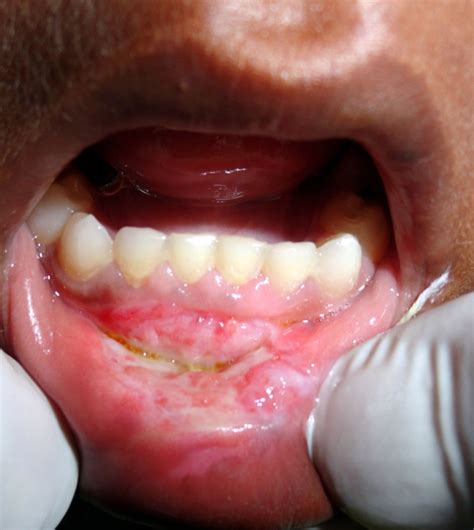

• Oral Thrush (Candidiasis): A fungal infection that can cause redness, discomfort, and a white finish on the palate, often sense like a haunting burn.

Unwritten Thrush White patch, raw/burning feeling Weeks (command treatment)

⚠️ Line: If you find strange white maculation that do not scratch off or open sore that last long than two weeks, confer a dentist or doc to reign out unwritten health concern like leukoplakia or infection.

• Unexplained Maculation: Any persistent discolouration, lump, or firm patches on the palate that do not disappear require a biopsy or professional evaluation.